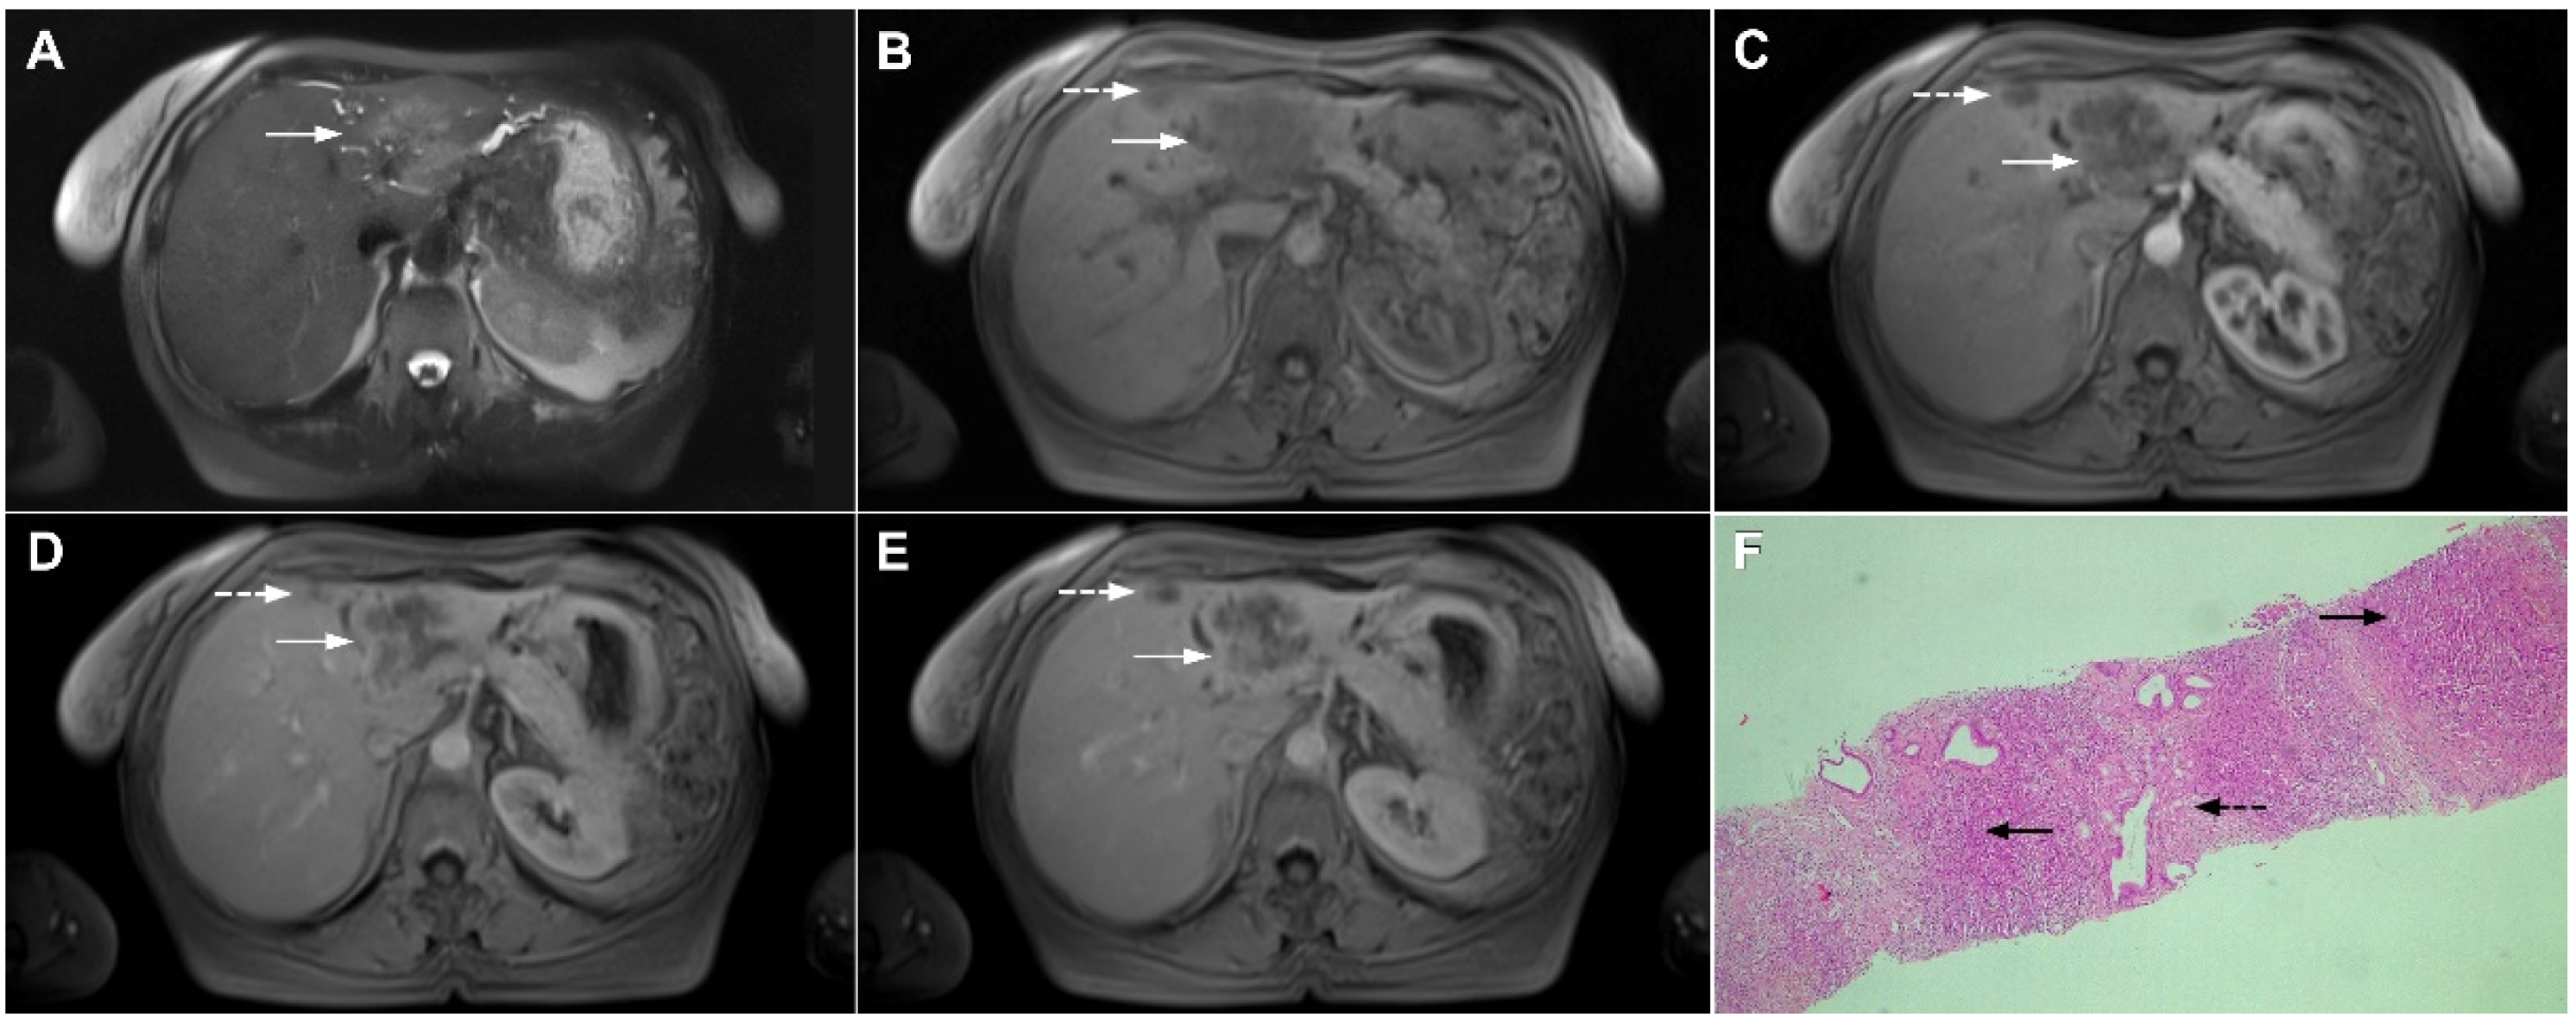

Figure 1.

Typical intrahepatic mass-forming cholangiocarcinoma in 68-year-old woman. On axial T2-weighted image a lobular heterogeneously hyperintense tumor (arrow) is seen, located centrally in the liver segment IVB (A). The lesion (arrow) is hypointense in a plain T1-weighted image (B) with irregular ring enhancements in the arterial phase (C) and progressive enhancement in the portalvenous (D) and delayed phase (E). Note the perilesional biliary dilatation. Hematoxylin and eosin (H&E) staining (F) showed cholangiocarcinoma (arrow) and normal liver parenchyma next to the tumor (dashed arrow); original magnification ×40.

However, in highly fibrotic lesions or in lesions with internal necrosis, central parts may remain non-opacified even on delayed images (Figure 2) [14].

Figure 2.

Mass-forming intrahepatic cholangiocarcinoma in 72-year-old man. Irregular heterogeneously hyperintense lesion (arrow) on T2-weighted image (A) located in liver segments IVB and III with peripheral biliary dilatation is shown. On a plain T1-weighted image (B) the lesion (arrow) is hypointense with only discrete ring enhancement in the arterial phase (C) but without detectable enhancements in the portal venous (D) and delayed phases (E). Hematoxylin and eosin (H&E) staining (F) showed poorly differentiated cholangiocarcinoma (dashed arrow); normal liver parenchyma is also shown (arrow); original magnification ×40.